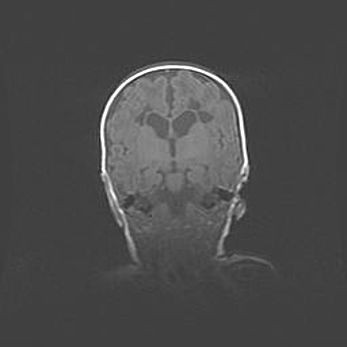

Множественные кисты обоих полушарий головного мозга, наибольшая из них в правой затылочной области. Ассиметричная атрофическая гидроцефалия.

Возраст: 7 месяцев

Вес: 5660 г

Пол: мужской

Окружность головы: 41,5 см

Срок гестации: 28-29 недель

Кисты головного мозга развиваются в результате многоочаговых некрозов вещества мозга и возникают вследствие перенесенной перинатальной инфекции, менингитов, энцефалитов, асфиксии, родовой травмы, расстройств мозгового кровообращения различного генеза. Образованию кист в веществе головного мозга плодов и новорожденных способствуют такие факторы, как высокое содержание в нем воды, недостаточная (или отсутствие) миелинизация и слабая астроглиальная реакция на повреждение.

Кисты могут сочетаться с гидроцефалией и другими поражениями головного мозга.